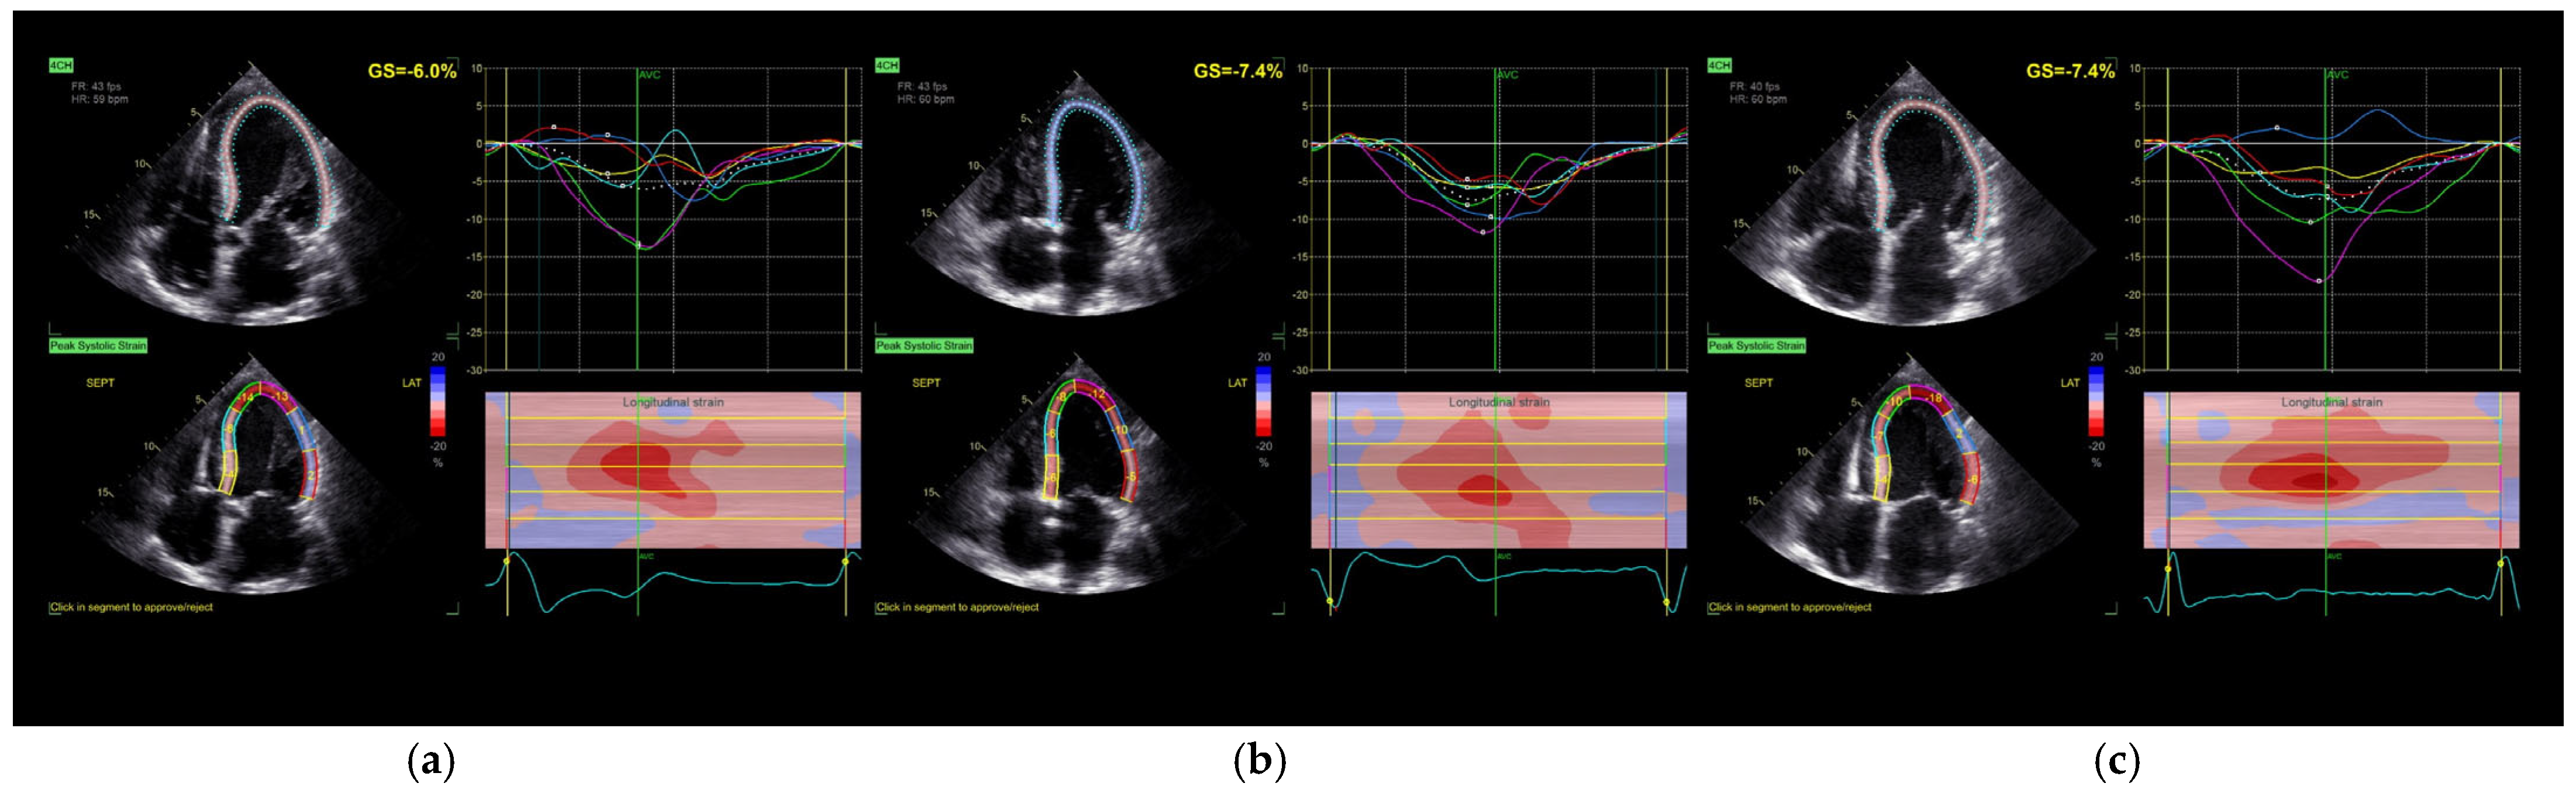

Figure 1.

Longitudinal strain assessment in the four-chamber view: (a) without stimulation; (b) BiV stimulation; (c) SyncAV stimulation. GS—global longitudinal strain; AVC—aortic valve closure.

Global longitudinal strain (GLS) of the left ventricle did not show statistically significant changes in response to either pacing strategy (p = 0.212), although a mild trend toward improvement was noted following biventricular pacing. Importantly, the time to peak longitudinal strain (Peak SL) was significantly reduced under both pacing modes compared to baseline (p = 0.015), reflecting improved mechanical synchrony. Additionally, SyncAV® pacing was associated with a prolongation of aortic valve closure time, suggesting enhanced contractile force [17].